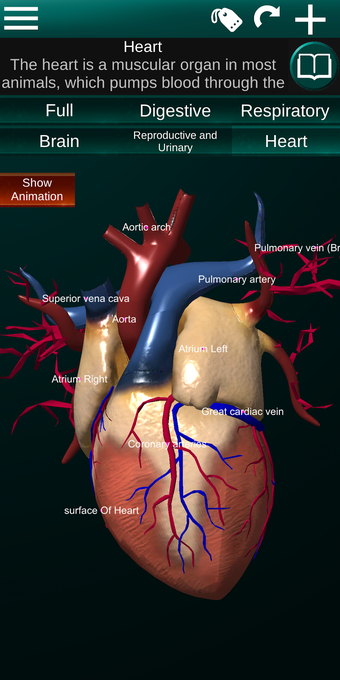

此应用程序显示人体器官的三维模型和所有器官的描述。

您可以触摸每个器官,如心脏、大脑、肺、生殖系统、肝脏、肠道、卵巢、睾丸、胃、肾脏等。

它对所有人都有用,甚至对学生也有用,因为每个解剖器官都以不同的颜色显示。

您可以使用该应用程序找出哪些是不同的身体器官以及它们的功能。